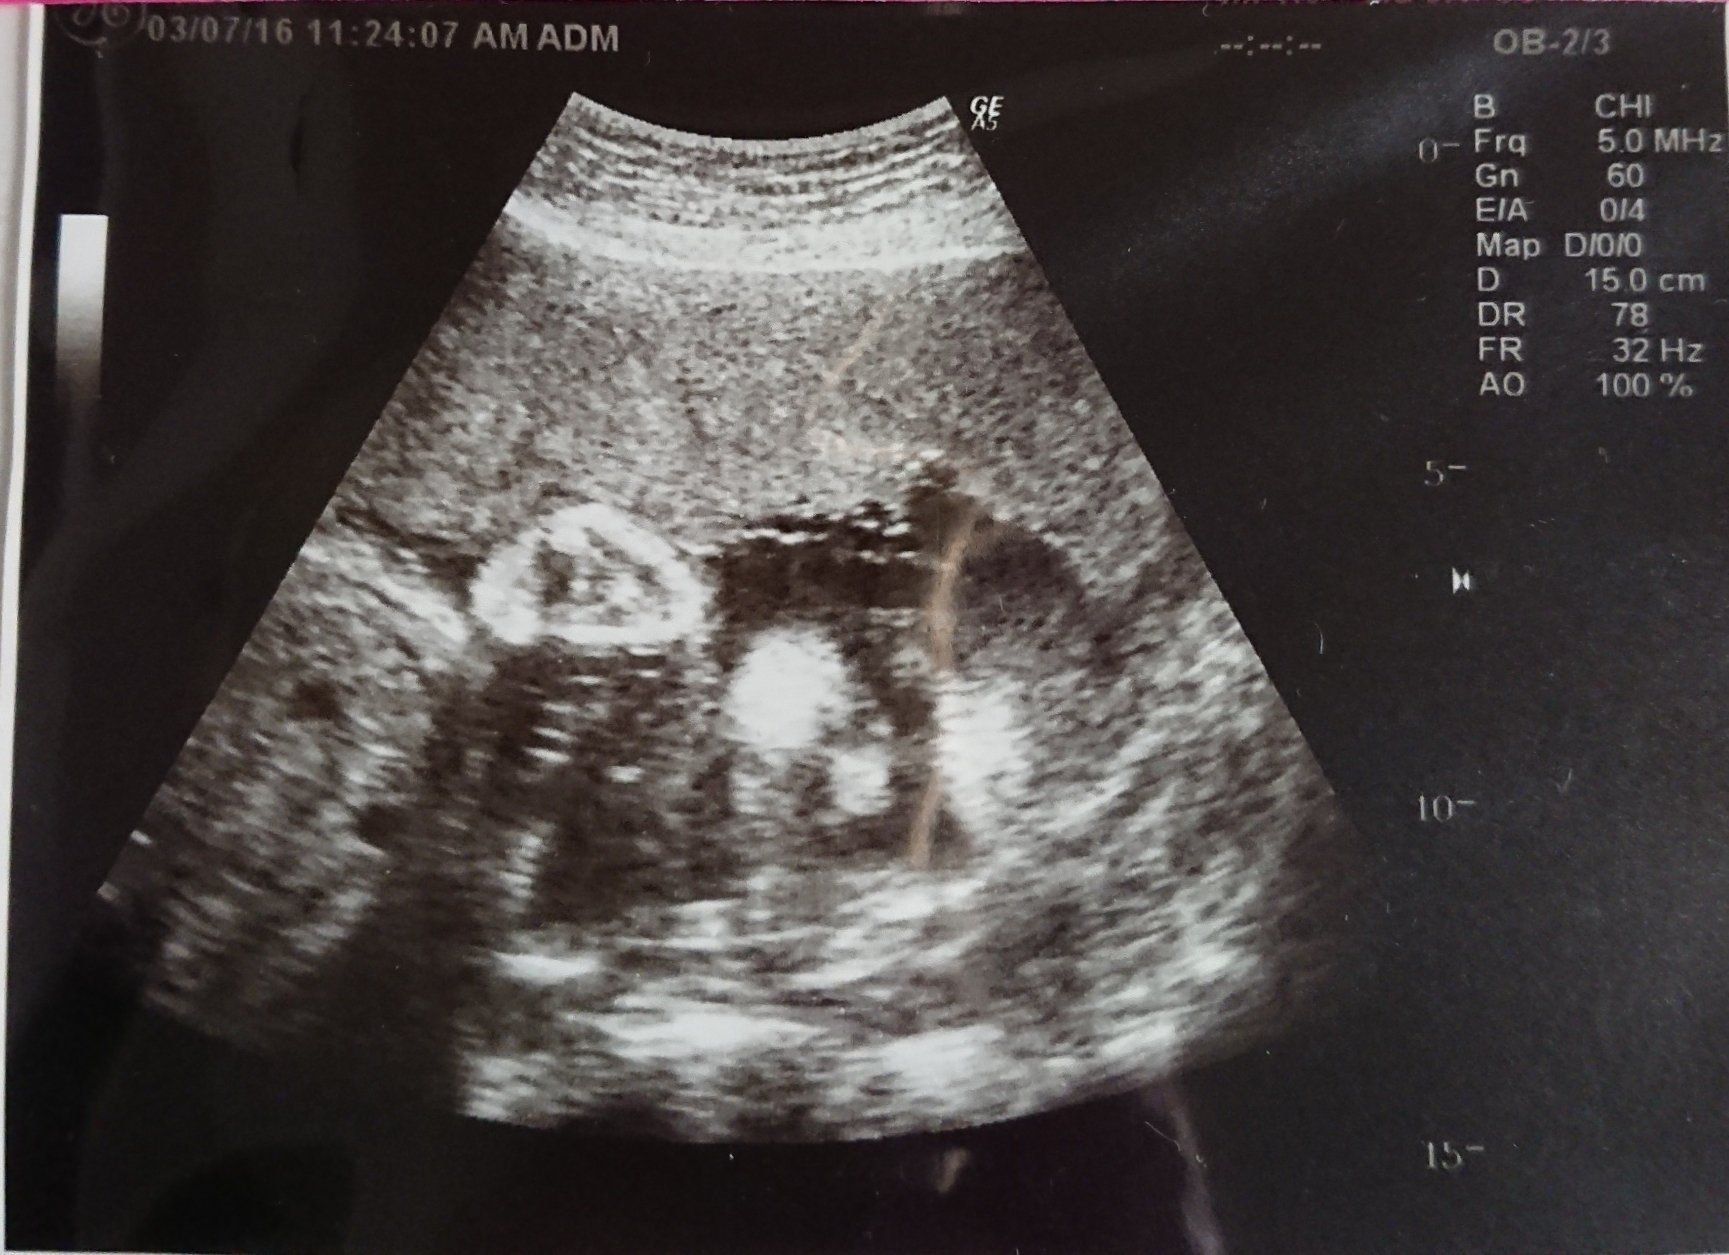

妊娠26週目 性別判明!赤ちゃんの名前が舞い降りた!

前回わからなかった性別がやっとわかりました。ドキドキして待っていると、先生が「女の子だよ! おしゃぶりの練習をしているのかな?」と。このエコー写真を見た時、突然ビビビッと感じ「メイ」と名付けようと決めました。